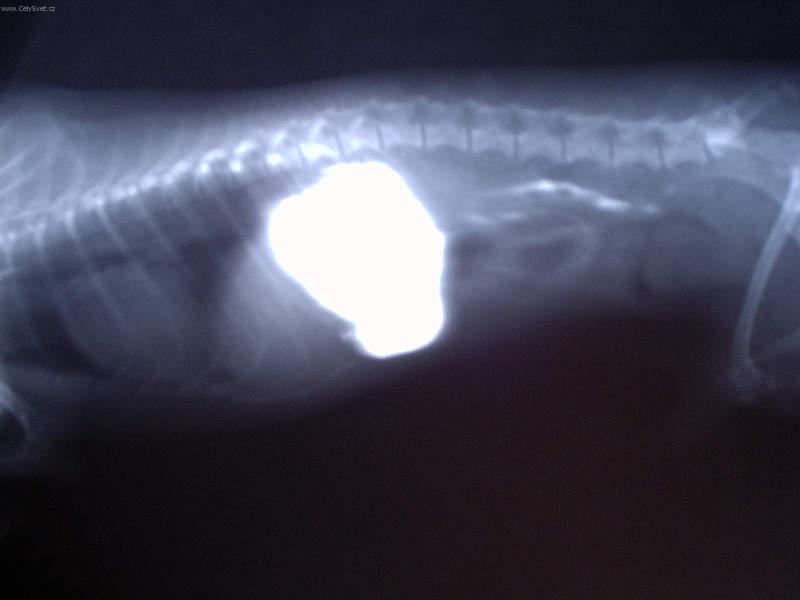

Fotogalerie > KOČIČÍ SVĚT: Veterinární poradna > Léčba interních onemocnění